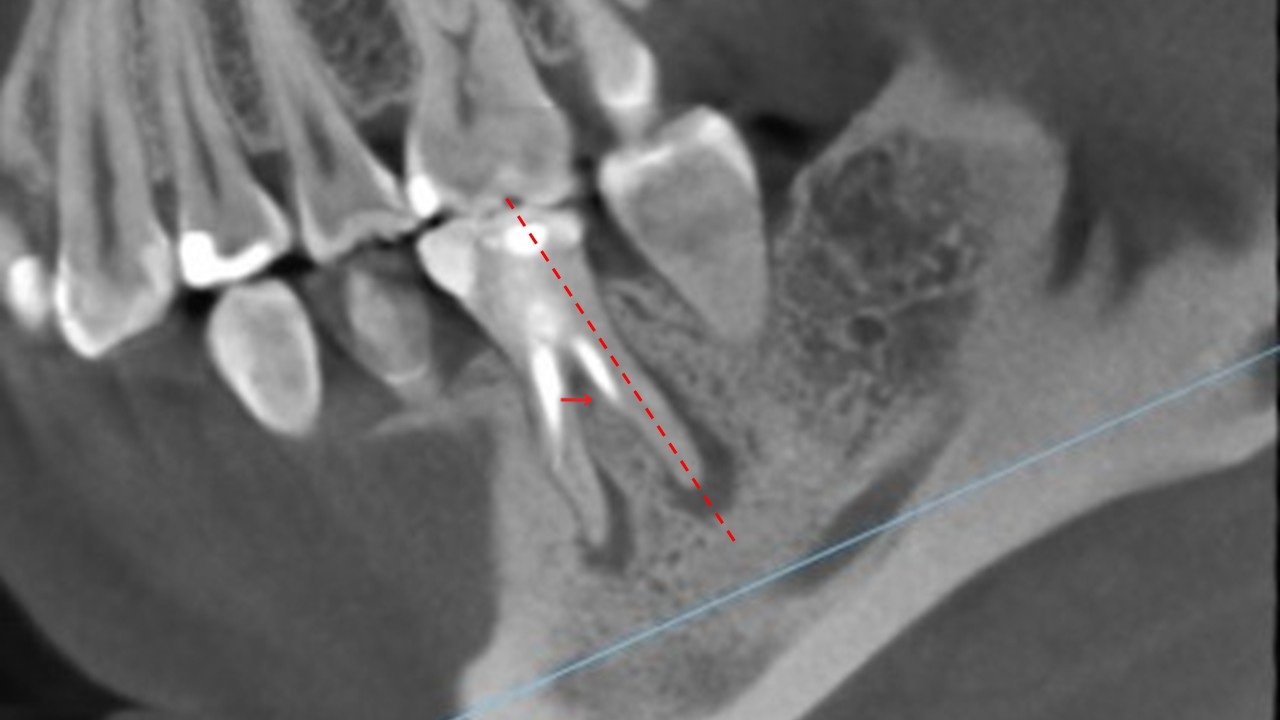

次はこちらの断面へ

遠心の歯根の断面を見てみます。

赤い矢印にありますが、この充填材はすでに根の内側に穿孔しています。

すでに内側に穿孔している充填材は右側の矢印のものです。途中で止まっています。

左側の根管は、左側へ突き抜けて穿孔し、その先が炎症を起こし、黒い影が見られます。

どちらの根の先も膿んで黒い影があります。

つまり、4根管のうち3根管は方向がそれて穿孔しています。